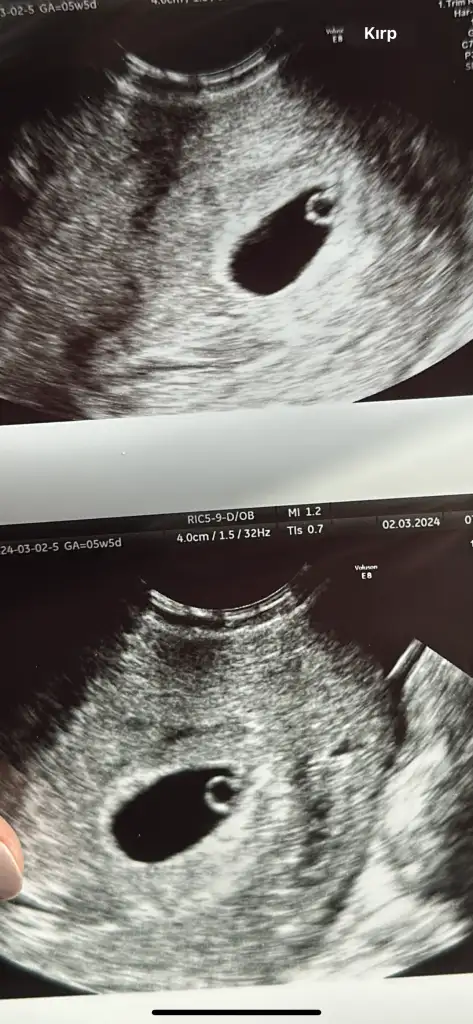

Kızlar keseden cinsiyet anlayanınız var mı 5hafta 5gün vajinal ultrason

Normal gözükmedi karından vajinalde gözüktü 5 hafta 5 günlük ama kalp atışı için 11 ine tekrar randevu verdi inşallah seninde vardır bebişim sağlıkla kucaklamayı nasip etsin rabbim hepimize kimseye de aratmasın inşallah ❤️